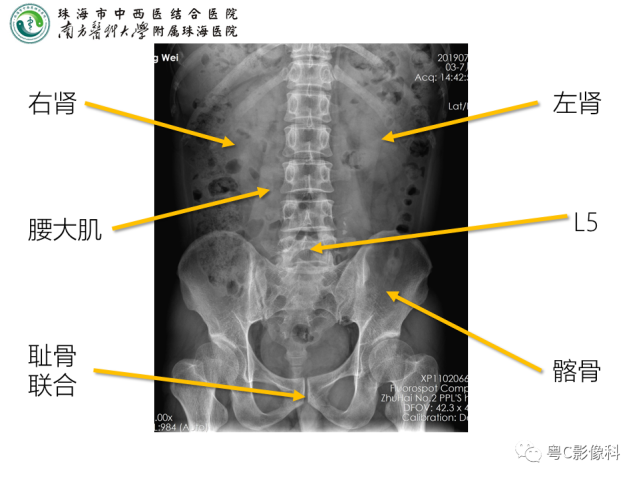

x线高清图谱 | 精致腹部解剖

图片尺寸1357x747